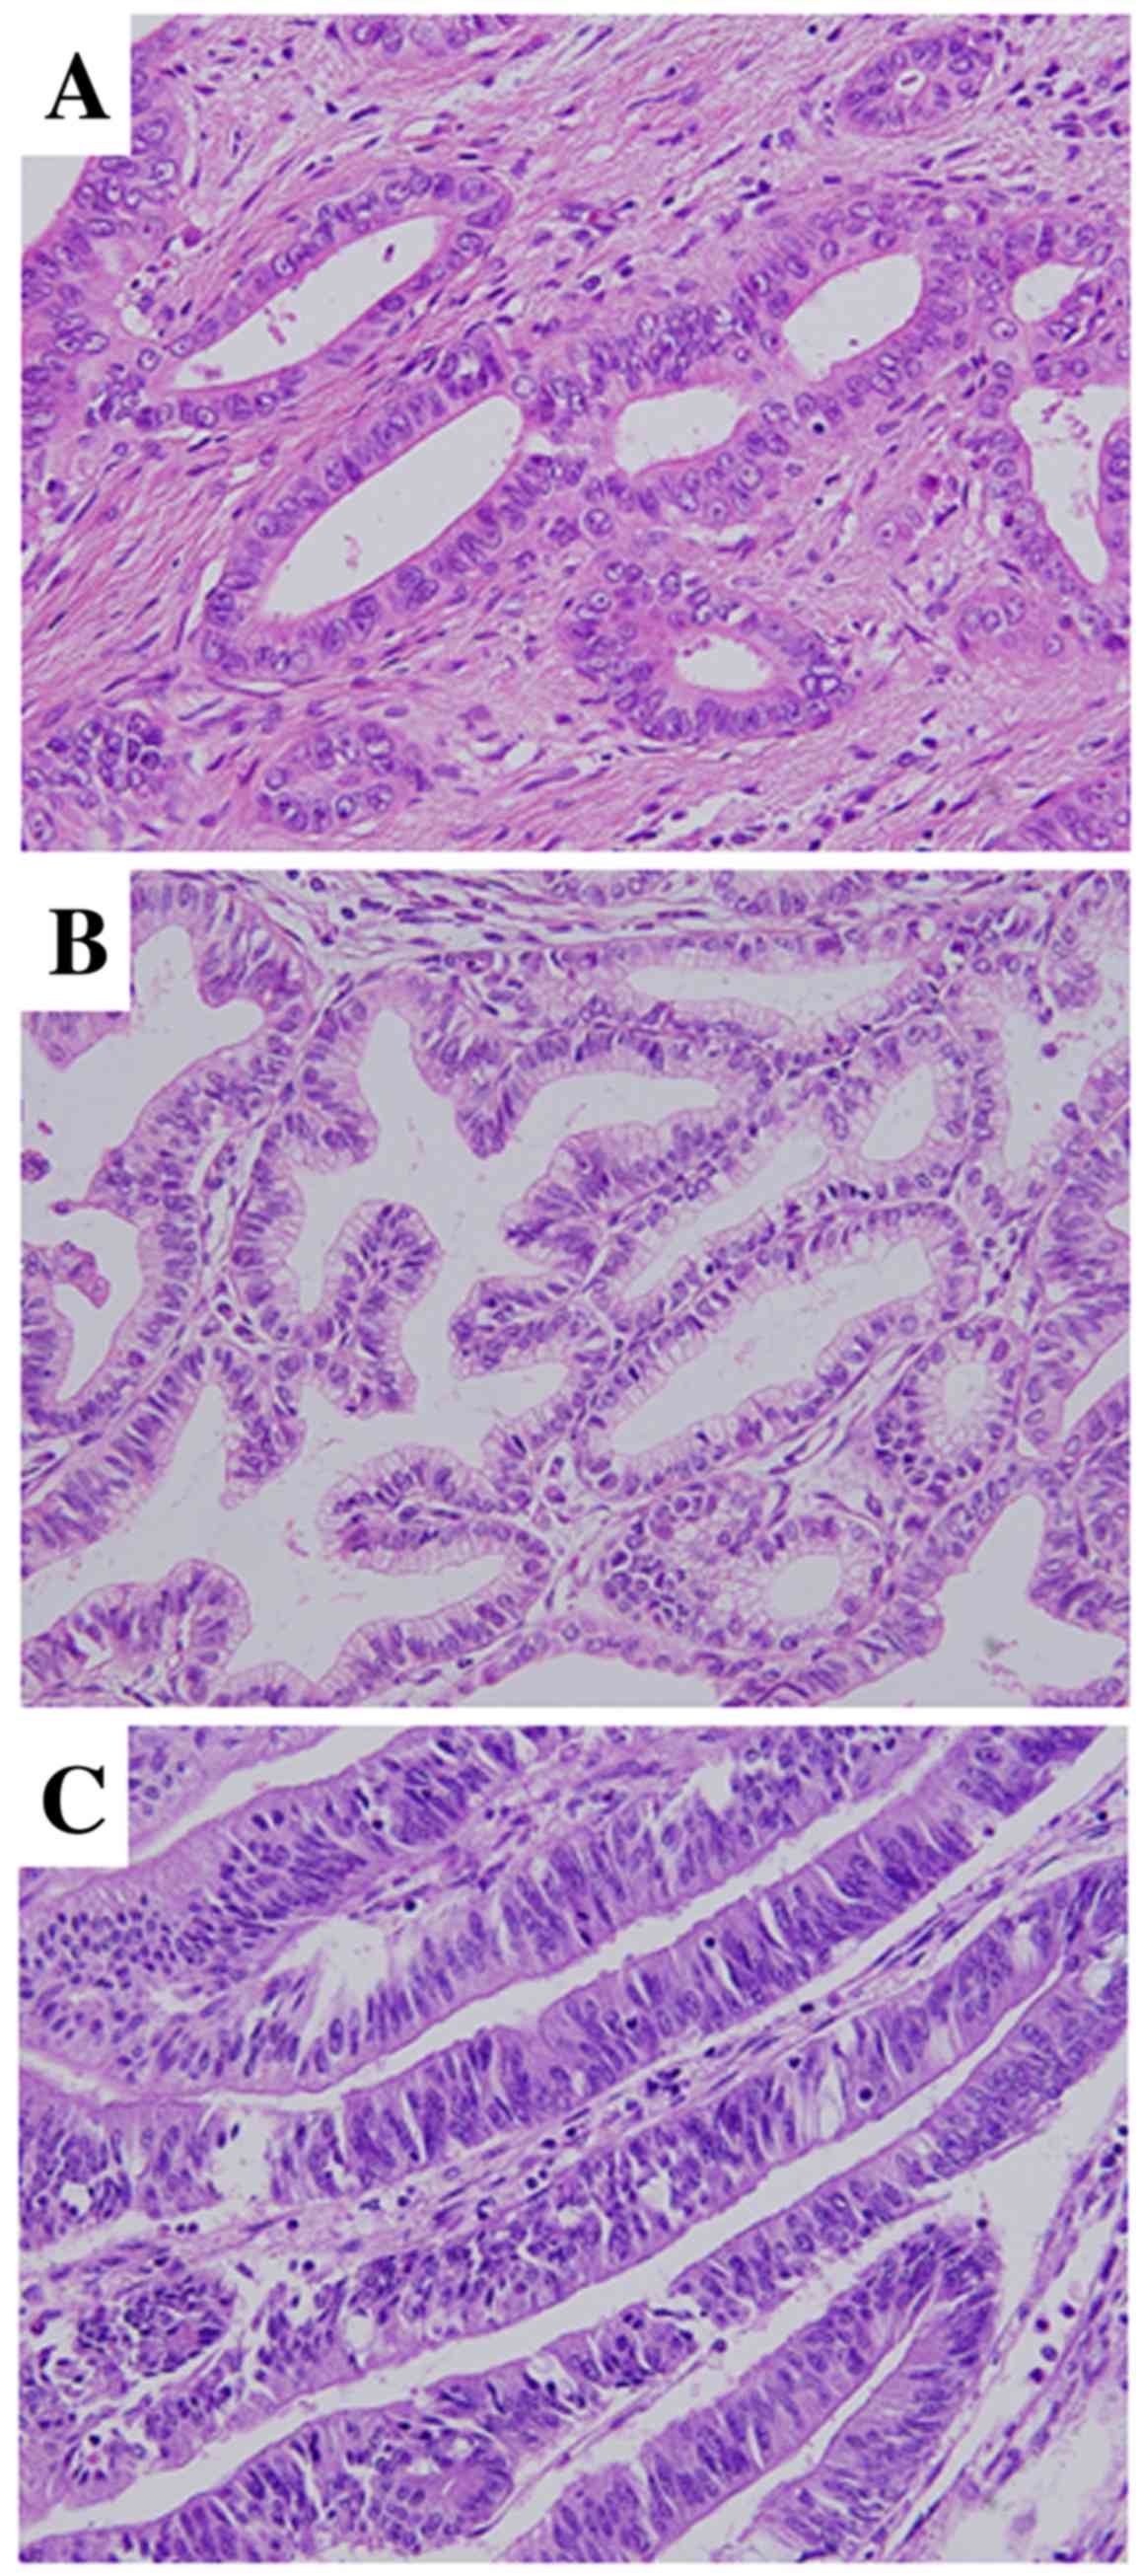

Фотографии медицинских исследований инсулиномы и синдрома Триады Уиппла